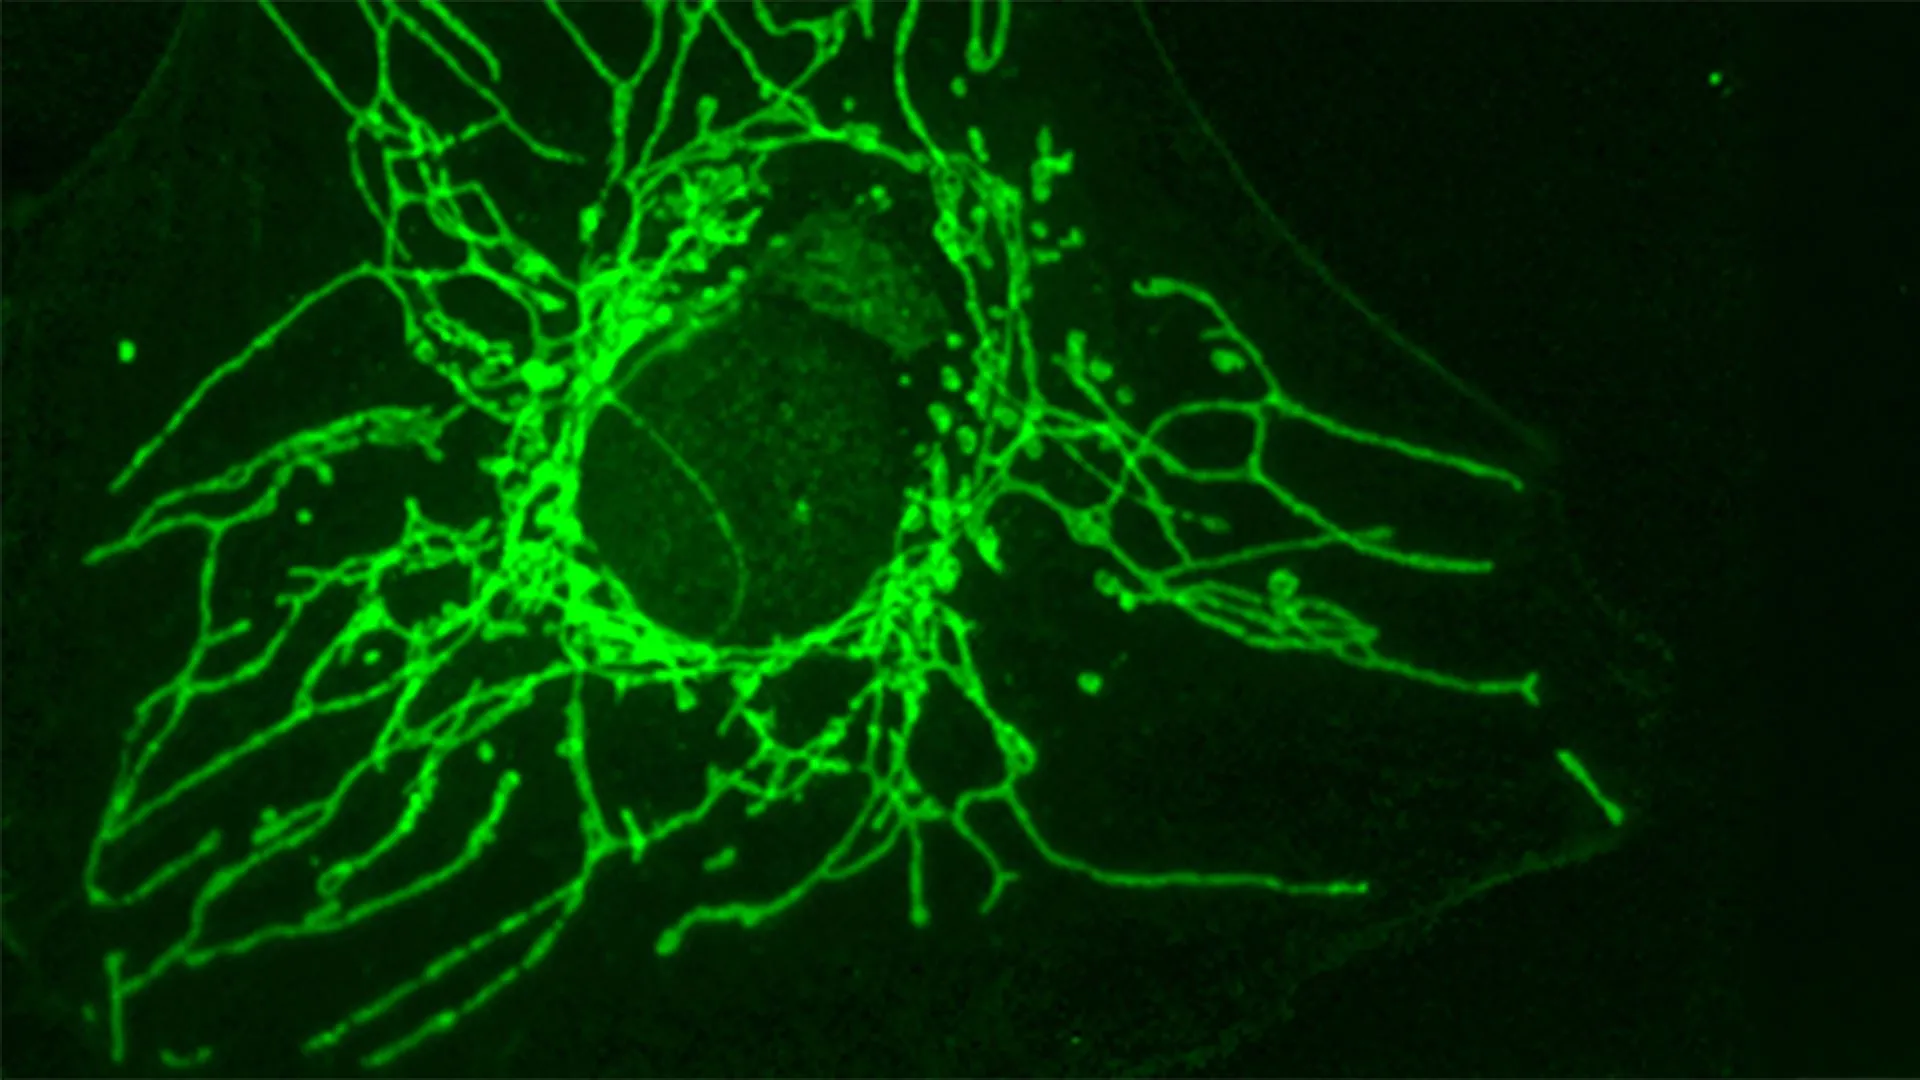

Working with Professor Roland Lill and his team at the University of Marburg, the researchers uncovered how D-Cys harms cancer cells.

“It blocks an essential enzyme called NFS1, located in the mitochondria — the cell’s ‘powerhouses’. This enzyme plays a key role in producing iron-sulfur clusters, small structures that are indispensable for many processes such as cellular respiration, DNA and RNA production, and maintaining genetic integrity,” explains Roland Lill.

When NFS1 is blocked, several critical cellular functions break down. Cancer cells experience reduced respiration, DNA damage increases, and the cell cycle stops. Together, these effects prevent the cells from continuing to grow and divide.